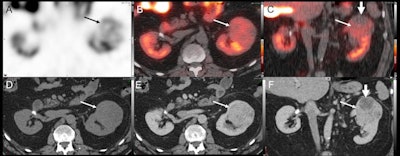

A U.S. group in Missouri analyzed scans from patients with biopsy-proven renal masses who underwent both SPECT/CT with technetium-99m sestamibi (Tc-99m) and contrast-enhanced CT. The team found SPECT/CT better distinguished between benign and malignant tumors.

The sensitivity and specificity of SPECT/CT for diagnosing nonconcerning lesions were 66.7% and 89.5%, respectively, compared with 10% and 75% for contrast-enhanced CT, according to the analysis. In addition, SPECT/CT correctly classified 80% of the RCC lesions, compared with 33.3% on contrast-enhanced CT.